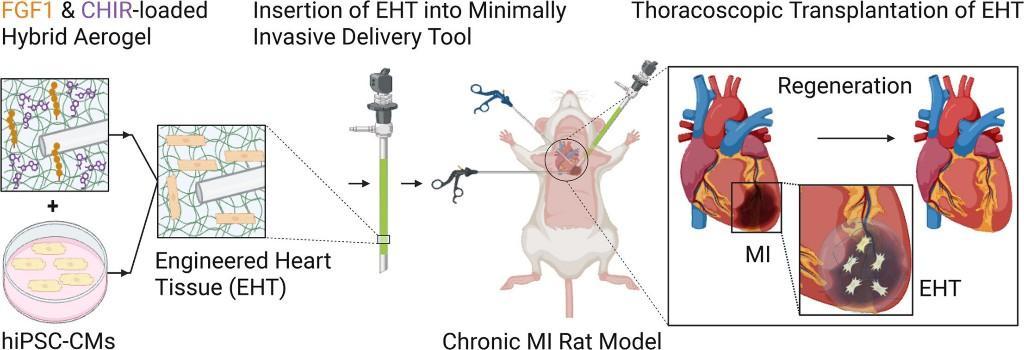

總編輯圈點 | 干細(xì)胞貼片無需大手術(shù)修復(fù)心臟,為心衰治療開辟新路徑